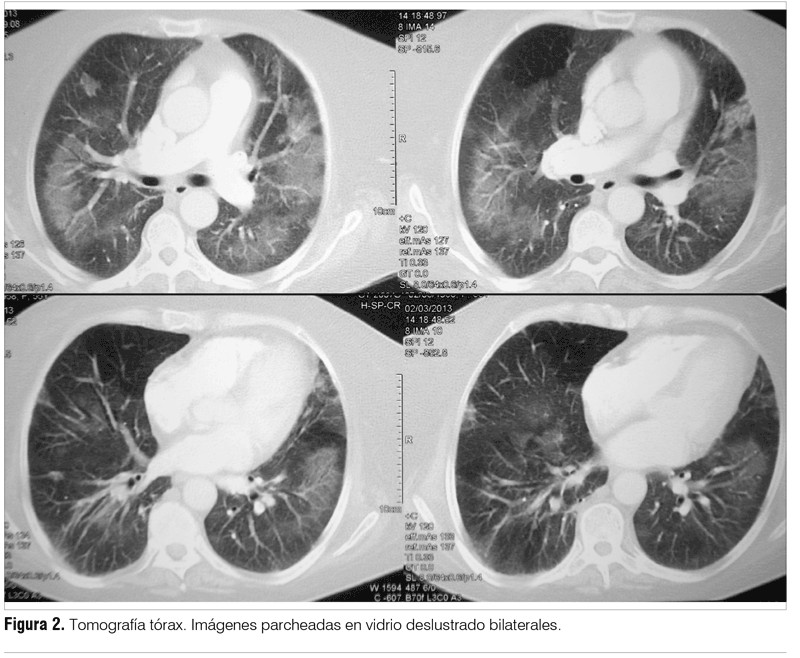

Dada la peoría clínica se inició tratamiento antibiótico empírico para cubrir gérmenes inespecíficos y neumocitosis con piperacilina, tazobactam y trimetoprim sulfametoxazol. Se solicitó nueva tomografía de tórax que evidenció un patrón parcheado en vidrio deslustrado de forma bilateral (figura 2) y una segunda fibrobroncoscopía con lavado bronquioalveolar, el resultado del lavado confirmó la presencia de Pneumocistis jiroveccii (PJ).